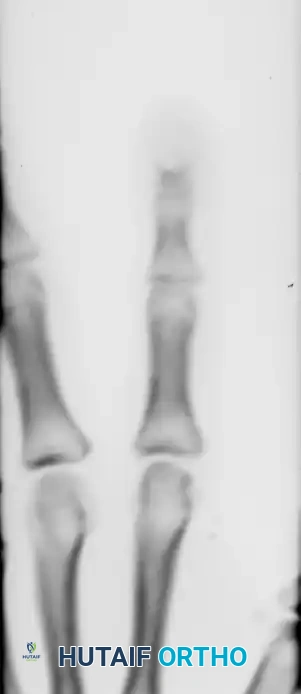

Radiographic Evaluation

The distal phalanx is the most common osseous site for an epidermoid cyst. When the cyst occurs at the base of a fingernail and invades the distal phalanx, it closely mimics the radiographic appearance of an enchondroma or a glomus tumor.

Figure 77-27 B: Anteroposterior radiograph demonstrating a soft tissue mass and well-circumscribed central bony erosion of the distal phalanx.

On radiographs, the cortex appears expanded, and a central lytic lesion is typically the only bony reaction. Unlike malignant lesions, there is usually a distinct sclerotic margin indicating a slow-growing, benign process.